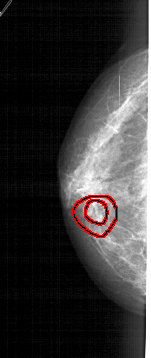

A_1938_1.LEFT_MLO

LEFT_MLO LINES 5101 PIXELS_PER_LINE 2506 BITS_PER_PIXEL 12 RESOLUTION 43.5 OVERLAY

FILE: A_1938_1.LEFT_MLO.OVERLAY

TOTAL_ABNORMALITIES 1

ABNORMALITY 1

LESION_TYPE MASS SHAPE IRREGULAR MARGINS SPICULATED

ASSESSMENT 5

SUBTLETY 2

PATHOLOGY BENIGN

TOTAL_OUTLINES 2

BOUNDARY

CORE